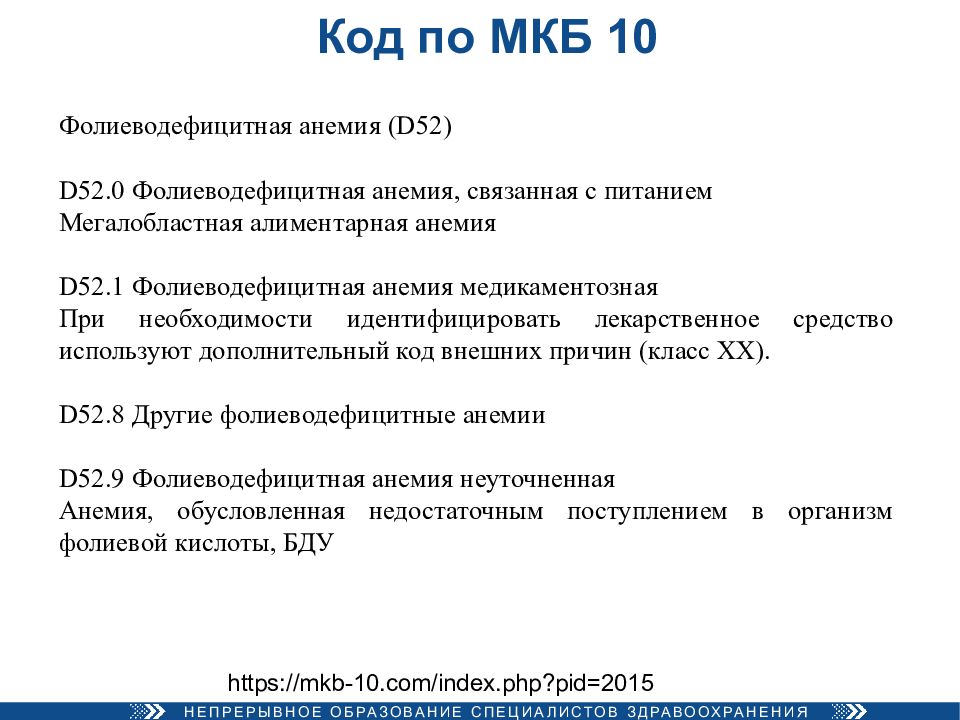

Код мкб 10 атерома головы

Код мкб 10 атерома головы 109 фото